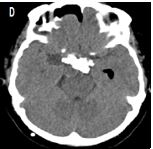

O uso de ressonância magnética de crânio para conferir a presencia de massa tumoral é mais fidedigna. Nas sequencias T1WI achamos sinal variável devido ao conteúdo do cisto, muitas vezes hiperintensidade devido ao material proteico, enquanto o componente tumoral sólido pode ter aspecto heterogêneo ou isointenso. No T2WI os cistos são tipicamente hiperintensos com focos hipointensos devido a calcificações. O T2 * / GRE / SWI encontramos um sinal “preto” que floresce secundário à calcificação ou sangue. São tumores que captam contraste na parte solida, mesmo sendo de origem benigna.

Volumosa lesão expansiva selar supraselar, heterogênea, solido cística. Ressonância Magnética, T1, corte coronal contrastada, volumoso componente cístico ocupando o III ventrículo, cístico com sinal hiperintenso, alto conteúdo proteico (A), sinal hipointenso em T1 coronal, na porção solida, com realce de contraste (B), sequência T2 mostrando áreas hipointensas sugestivas de calcificação (C), TC de crânio demonstrando as calcificações intratumoral..